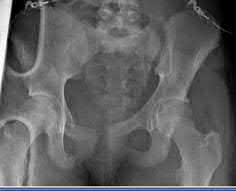

An 82-year-old woman falls and sustains the fracture shown in figure A. She denies any history of dislocation or prodromal pain prior to her fall. What is the most appropriate treatment?

The radiograph demonstrates a periprosthetic femur fracture extending to the tip of the stem. The long spiral fracture is consistent with a loose implant. The bone stock is sufficient. Therefore, this fracture pattern would classify as a B2 using the Vancouver classification system. The Vancouver classification for periprosthetic femoral fractures is simple yet incorporates all the pertinent factors such a location, stem fixation, and bone stock. Type A is a trochanteric fracture- lesser or greater. These can be treated non-operatively usually and ORIF if symptomatic. Type B fractures are around or just below the stem and are subdivided into three types. Type B1 is a fracture with a well fixed stem.

The treatment is cable plating or allograft struts or a combination of the two. Type B2 is a fracture with a loose stem with good bone stock. The treatment is a cementless porous coated long stem atleast two diameter length past the

fracture site. Type B3 is a fracture with a loose stem and comminution. For younger patients, use cementless porous coated long stems with allograft struts. For older patients, consider a tumor prosthesis. Cement fixation is sometimes necessary Type C is a fracture well below the stem tip. These can be treated independently of the prosthesis.

Springer et al showed optimal outcomes with revision involving long extensively-coated femoral stems for Vancouver B fractures.